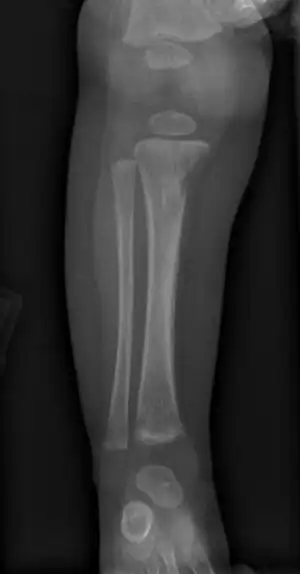

Wimberger corner sign; X-rays of (a) lower limbs (AP view) and (b) upper limbs (AP view) showing resolution of metaphyseal erosions and periosteal reaction

a) X-ray of the lower limb (AP view) showing proximal tibial metaphyseal erosions along with periosteal reaction and (b) X-ray of the upper limb (AP view) showing distal tibial and fibular metaphyseal erosions with periosteal reaction